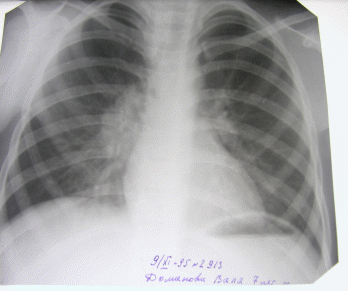

При рентгенологическом исследовании органов грудной клетки выявлены изменения.

(1) Представлена рентгенограмма органов грудной клетки в прямой проекции.

- Постановка больного правильная;

- Костно-рёберных изменений не наблюдается;

- Костно-диафрагмальные синусы свободные;

- Тень средостения без особеностей;

- Легочной рисунок усилен.

- Корень правого лёгкого не структурный, левого мало структурный.

- Купола диафрагмы правильной формы, правое на уровне 5 м/р, левое 6 м/р.

- Патологическое образование располагается в корне правого лёгкого, образовано за счёт увеличения лимфатических узлов.

- Форма тени имеет неправильную овальную форму;

- Тень средней интенсивности;

- Структура неоднородная.